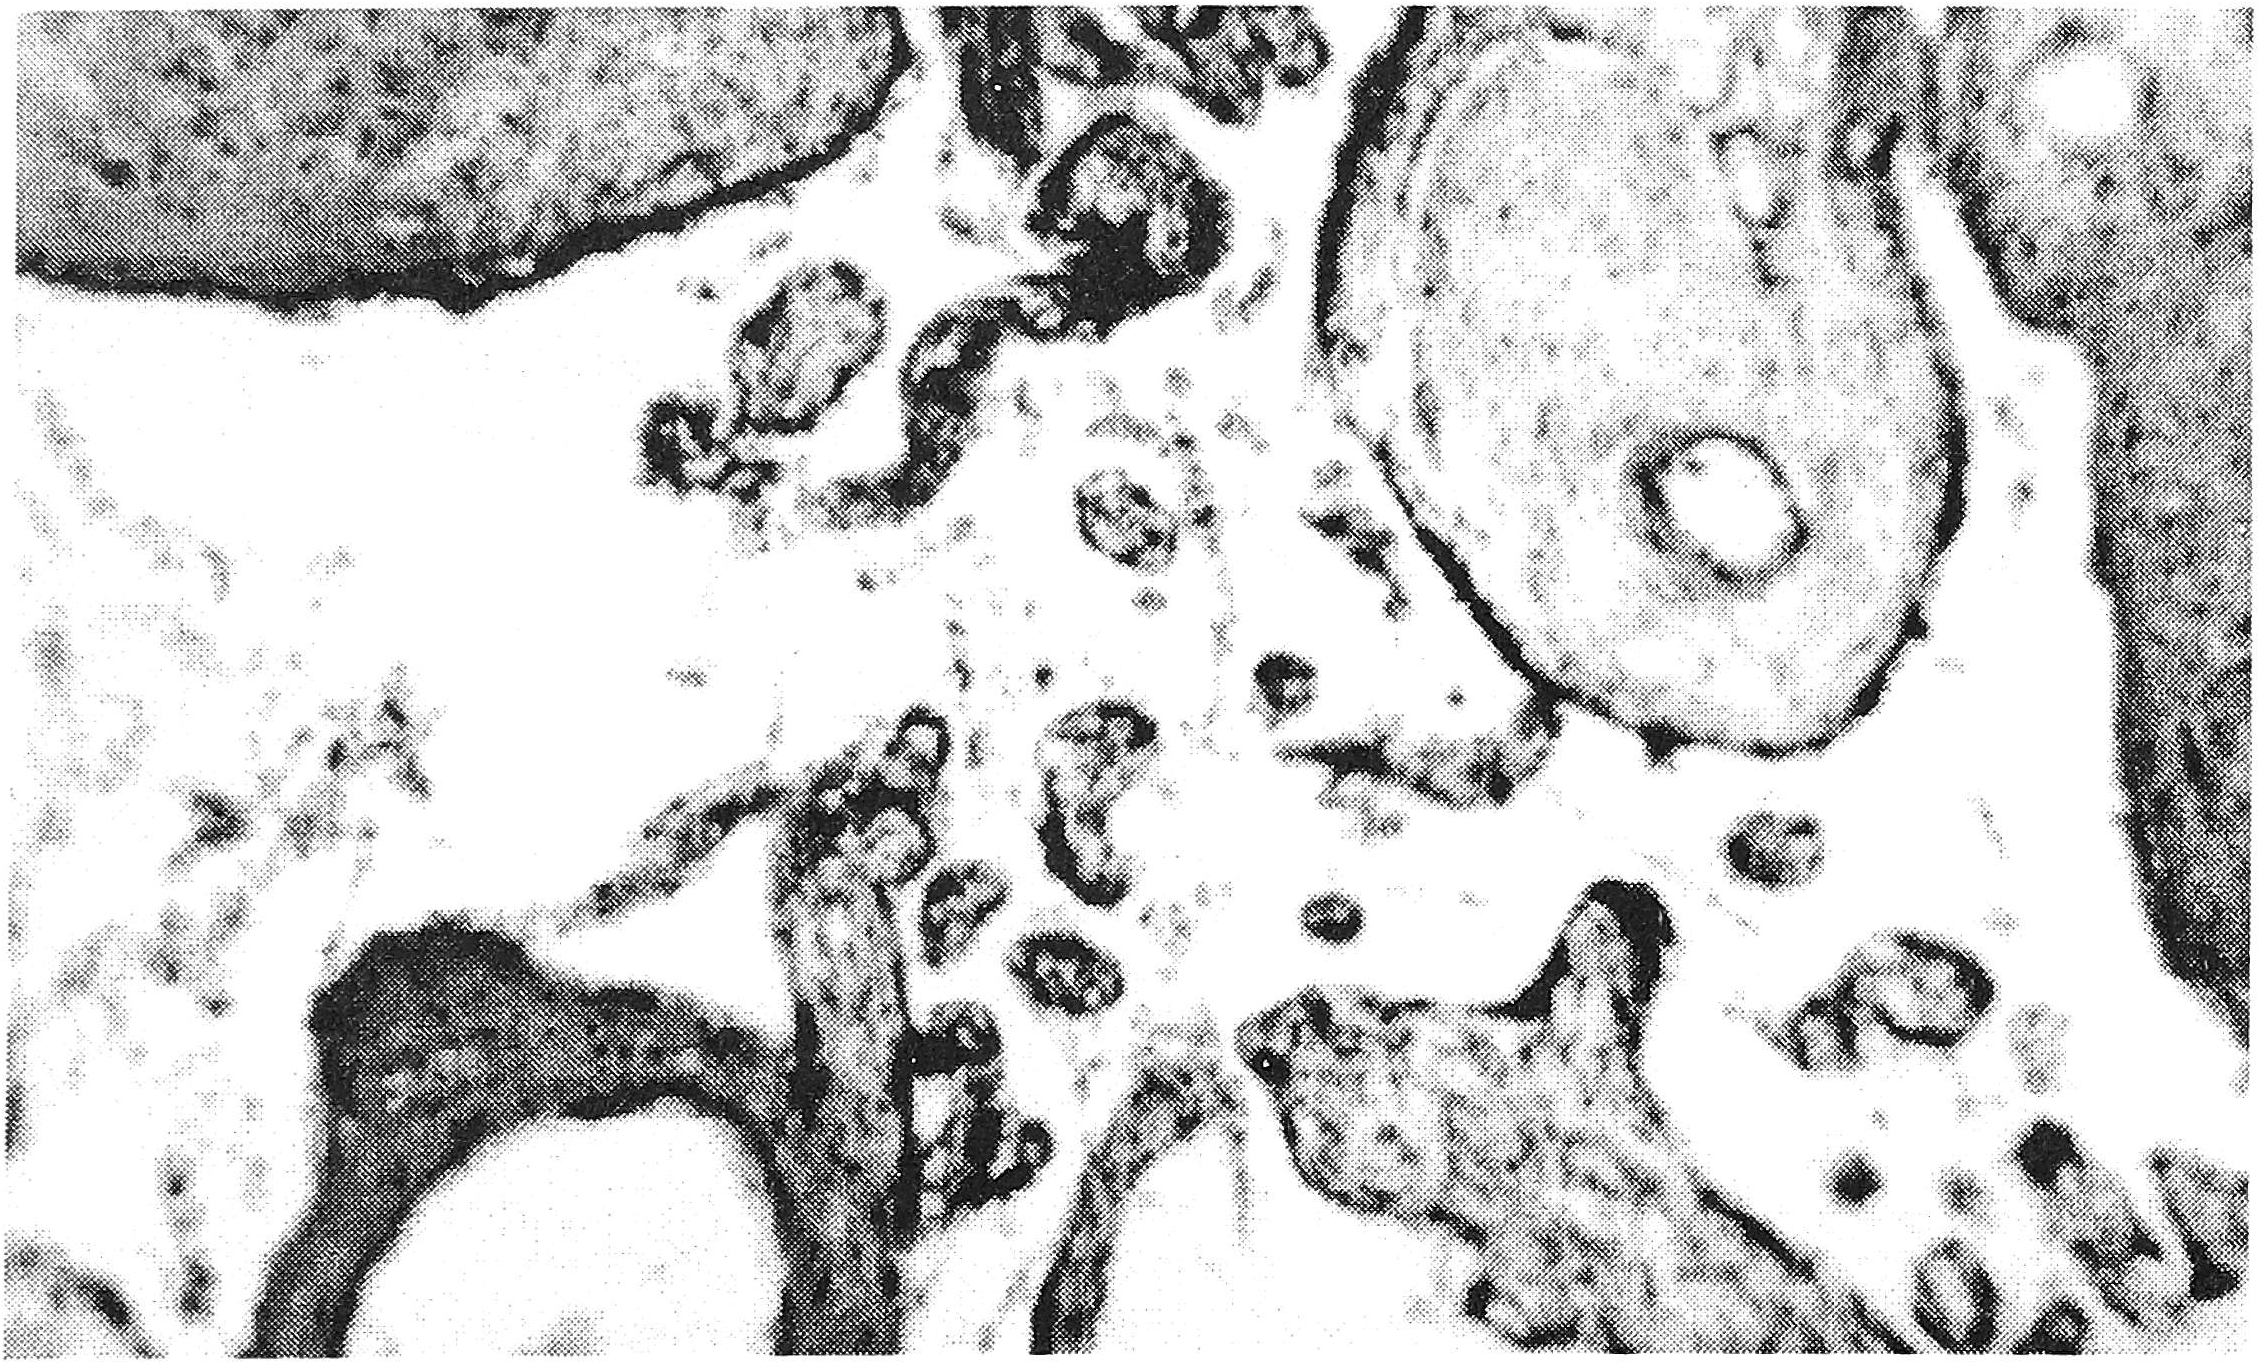

Воспалительные изменения отмечались в 90%, в основном носили характер виллузита и интервиллузита (см. рисунок) в половине случаев наблюдались слабовыраженные лимфоидные васкулиты в стволовых ворсинах, а в 90% - межворсинчатые кровоизлияния различной интенсивности, в основном - субхориальной локализации.

Рис. 1. Интервиллузит в плаценте женщины с дефицитом массы тела в сочетании с пиелонефритом.